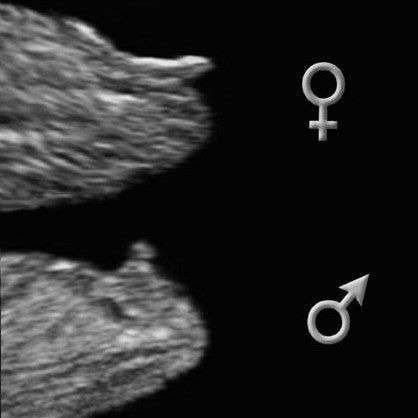

УЗИ, КТГ, доплерСходили мы с мужем на узи 24 ноября. По М был срок 12+6. Зашли, я легла на кушетку, муж сел рядышком. Врач только села возле аппарата, я ей говорю:"если можно будет рассмотреть, скажите нам пожалуйста пол". Она улыбнулась и говорит:"если малыш даст рассмотреть, обязательно скажу". Выдавливает гель, начинает водить датчиком и сразу объявляет:"да тут мальчик у вас 100%!" Мы и сами смотрим в экран и отчетливо видим как у малыша раскинуты ножки и посерединке наше сладкое хозяйство😊 ой, какие у нас с папой были эмоции, это словами не передать!!! Мы так мечтали о сынульке, дочечки так хотели братика!!! И вот он, лежит, то трет глазки, то пальчик сосет😍наше чудо маленькое, наш сынишка!!!!❤❤❤

С малышком все хорошо, все параметры соответствуют сроку 13 недель. КТР 67мм, ЧСС 161 удар в мин. Сердечко послушали, пальчики на ручкахи ножках пересчитали, все органы проверили, ТВП 1,8мм, костная часть спинки носа 1,7 мм. Плацента по передней стенке матки, ШМ 44 мм. Все хорошо!

Врач нам дала фотографии, вот наше чудо